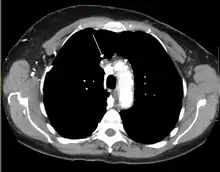

The main techniques of diagnosing SVCS are with chest X-rays (CXR), CT scans, transbronchial needle aspiration at bronchoscopy and mediastinoscopy.[6] CXRs often provide the ability to show mediastinal widening and may show the presenting primary cause of SVCS.[6] However, 16% of people with SVC syndrome have a normal chest X-ray. CT scans should be contrast enhanced and be taken on the neck, chest, lower abdomen, and pelvis.[6] They may also show the underlying cause and the extent to which the disease has progressed.[6]